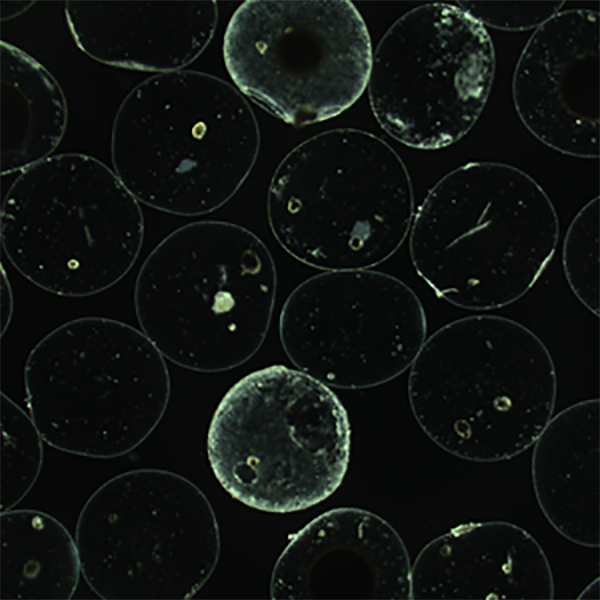

Thrilled to share that our review "Biomaterials for Personalized Cell Therapy" is now available online in #AdvancedMaterials! @LisaRVolpatti @AdvSciNews @kochinstitute

Scientist at Pyxis Oncology | PhD from @MITDeptofBE Langer and Anderson labs @kochinstitute